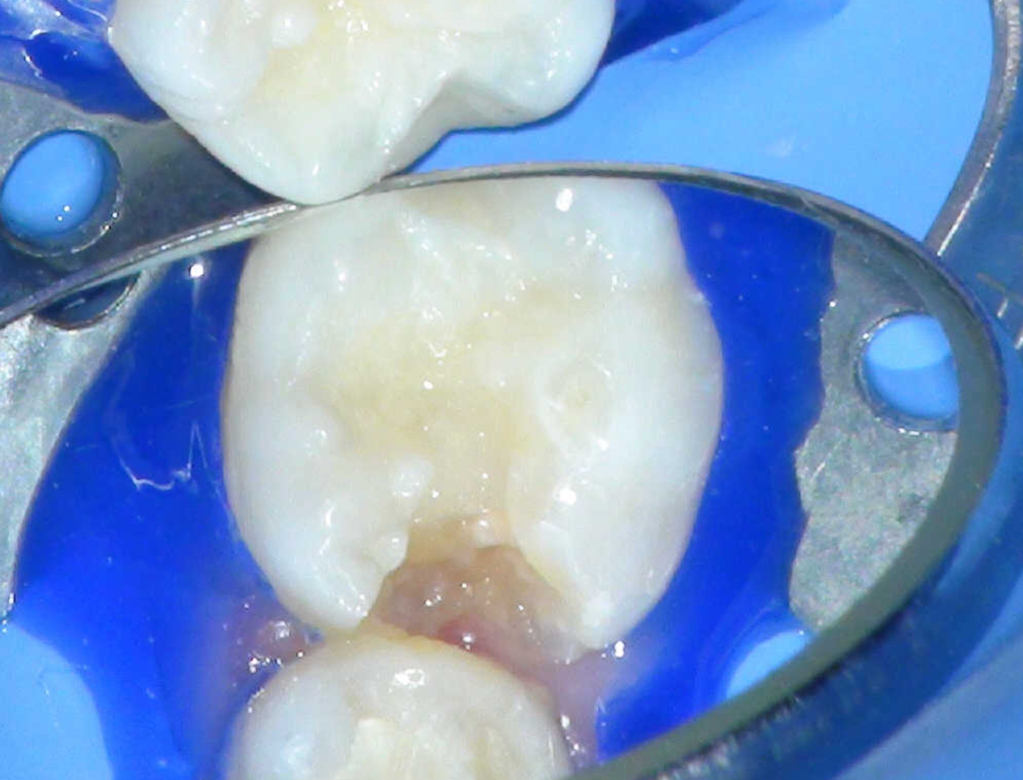

Pulpotomía biodentine + reco preendio

Pulpotomía diente temporal